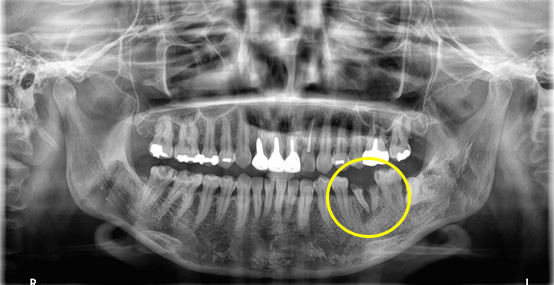

この症例では、抜歯する歯の周囲で骨が少し痩せている状態でした。

そのため、インプラントをしっかり支えるために、骨造成(骨を補う治療)を同時に行い、インプラントを埋入しました。

術前の状態

一次手術後のレントゲン写真です。

吸収していた骨の部分は人工の骨を足すことで無事に回復することができています。

手術後は大きなトラブルもなく、しっかり咬めて、違和感がない状態で、現在も良好に経過しています。